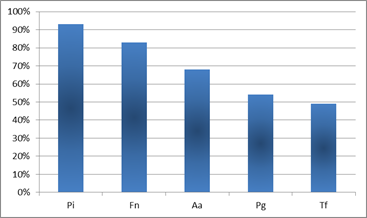

Los microorganismos que aparecieron con mayor prevalencia en los cuadros de Periodontitis Agresiva fueron P. intermedia y F. nucleatum. Éstos aparecieron en el 93% y 83% de los pacientes respectivamente. Le siguió en incidencia A. actinomycetemcomitans, microorganismo que se correlaciona fuertemente con los cuadros de Periodontitis Agresiva 9,11-12,16. A.actinomycetemcomitans apareció en el entorno del 70% de los pacientes estudiados (Graf. 1).

Cuando se hace la distinción entre Periodontitis Agresiva Localizada y Generalizada, la microbiota se diferencia poniendo en relieve la distinta etiopatogenia microbiológica de ambos cuadros. Cabe resaltar, que de los cuadros agresivos estudiados, el 60% de los casos correspondió a casos localizados y el 40% a cuadros generalizados. Es por este motivo que al estudiar la microbiota de los cuadros agresivos sin distinguir entre localizados y generalizados, los porcentajes de prevalencia están condicionados por el mayor número de casos localizados.